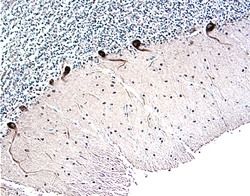

Parkin antibody in Human Brain by Immunohistochemistry (IHC-P).

Parkin in Human Brain.

Parkin was detected in immersion fixed paraffin-embedded sections of human brain (cerebellum) using 15 µg/mL Goat Anti-Human Parkin Antigen Affinity-purified Polyclonal Antibody (Catalog # AF1438) overnight at 4 °C. Tissue was stained with the Anti-Goat HRP-DAB Cell & Tissue Staining Kit (brown; Catalog # CTS008) and counterstained with hematoxylin (blue). View our protocol for Chromogenic IHC Staining of Paraffin-embedded Tissue Sections.